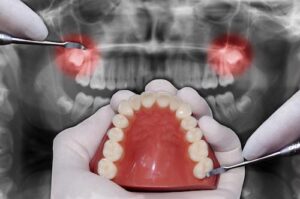

When your wisdom teeth don’t come through correctly, they’re said to be impacted. This can result in complications such as discomfort, swelling, and infection. These symptoms can be relieved by having your wisdom teeth removed.

They may get partially embedded in your gums or develop at an angle. This is referred to as an impacted wisdom tooth. Even if impacted wisdom teeth aren’t producing any symptoms, they don’t necessarily need to be removed.

However, the location of an impacted wisdom teeth can make it easier for food and germs to become trapped around the gum. This can result in inflamed and painful gums (pericoronitis), tooth decay, and infection. If you’re experiencing these symptoms, your dentist may advise you to have the impacted tooth extracted.